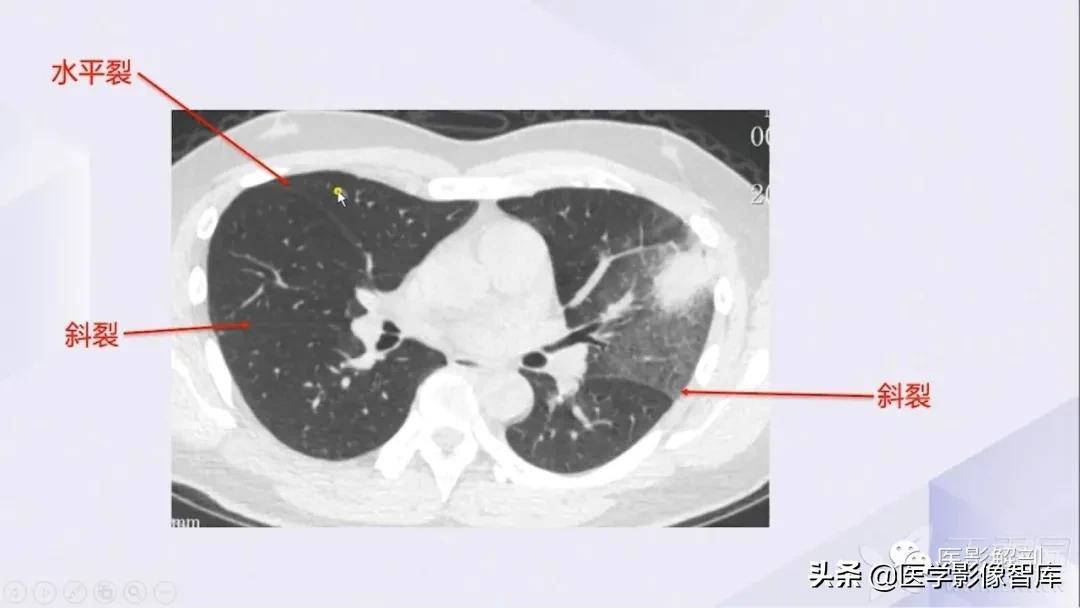

肺部CT解剖(高清图谱)